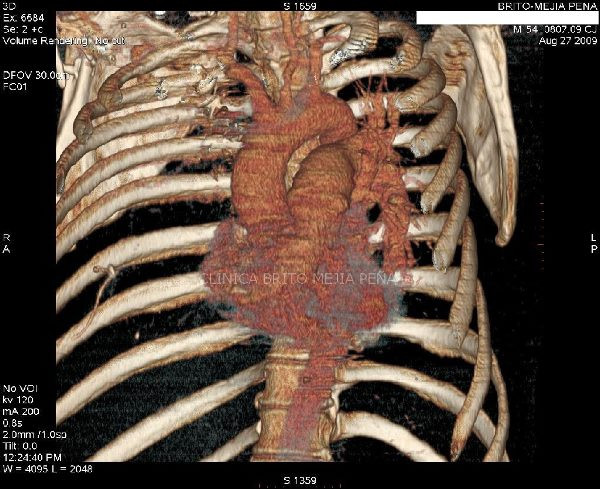

Trombosis arteria pulmonar 3D